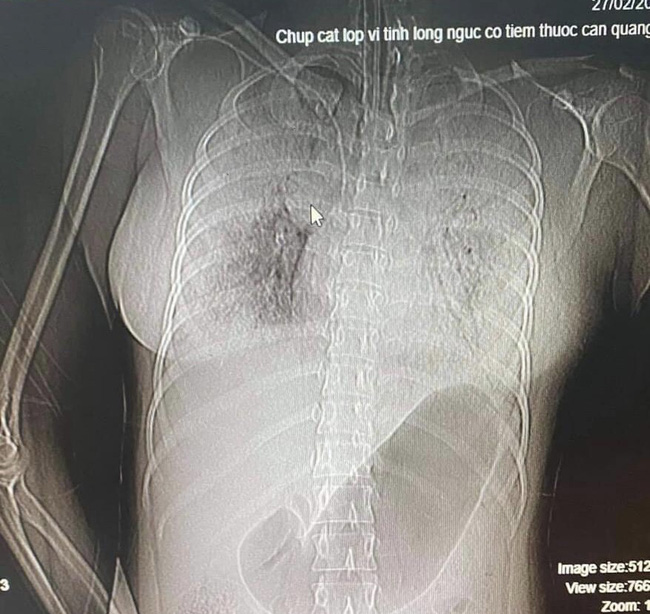

Hình chụp cắt lớp CT Scan lồng ngực bệnh nhân.

Tại đây, bệnh nhân rơi vào tình trạng thiếu máu nặng, rối loạn đông máu do ho ra máu lượng nhiều. Bên cạnh đó, phổi bệnh nhân đầy máu, chẩn đoán hội chứng chảy máu phổi (xuất huyết phế nang lan tỏa). Dù được tích cực cứu chữa nhưng bệnh nhân đã không qua khỏi và tử vong vào ngày 28/2 với chẩn đoán sốc mất máu do chảy máu trong phổi.